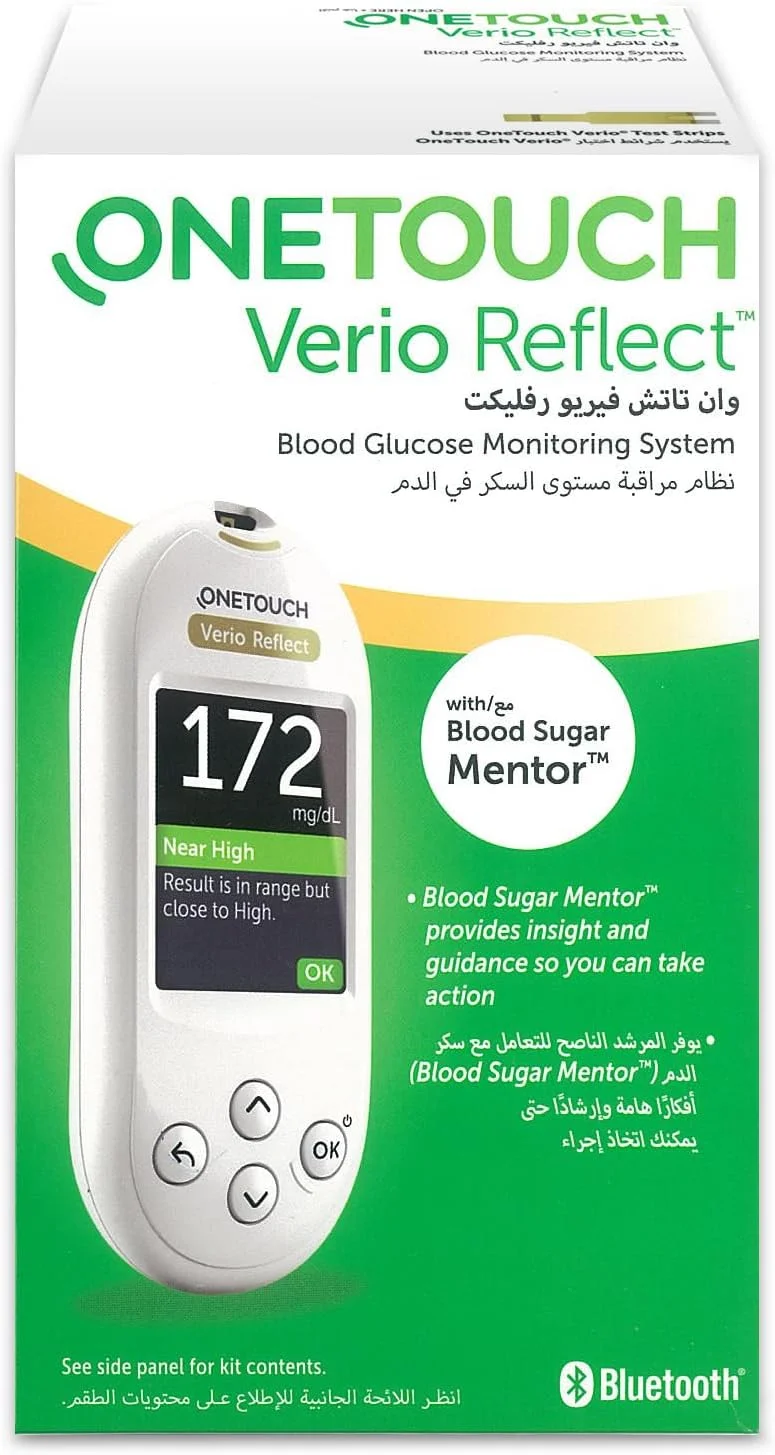

دستگاه تست قند خون معمولاً شامل یک دستگاه نمایشگر، نوار تست و قلم خون گیری (لنست) است. طراحی این دستگاه ها کاملاً جمع وجور و قابل حمل است؛ ابعادی کوچک و وزنی سبک که در کیف یا جیب جا می گیرد. صفحه نمایش بزرگ و خوانا، دکمه های کاربردی و گاهی قابلیت هایی مثل حافظه داخلی برای ذخیره نتایج یا اتصال به اپلیکیشن موبایل، از ویژگی های کلیدی آن است. نوارهای تست مخصوص هر برند، دقت بالا در اندازه گیری، سرعت پاسخ (بین ۵ تا ۱۰ ثانیه) و نیاز به حداقل مقدار خون از دیگر امکانات مهم دستگاه تست قند خون است. برخی مدل های جدید حتی فاقد نیاز به کدگذاری بوده و تنها با قرار دادن نوار و قطره خون، نتیجه را دقیق نمایش می دهند. رنگ بندی معمول دستگاه ها اغلب مشکی، سفید یا طوسی است که ظاهر حرفه ای به آن می دهد.

در بازار، انواع دستگاه تست قند خون با امکانات و قیمت های مختلف در دسترس هستند. مدل های پایه، عملکرد ساده دارند و برای استفاده خانگی و روزانه مناسب اند. این مدل ها عموماً بدون حافظه یا با حافظه محدود هستند. مدل های پیشرفته تر دارای صفحه نمایش رنگی، اتصال بلوتوث، نرم افزار تحلیلی و حافظه بالا برای ذخیره چندصد نتیجه اند. برخی مدل ها حتی قابلیت اندازه گیری هم زمان چند پارامتر مانند کتون خون یا کلسترول را نیز دارند. تفاوت در سرعت پاسخ، نوع نوار مصرفی، ظرفیت حافظه و ویژگی های جانبی می تواند انتخاب شما را تحت تأثیر قرار دهد. اگر دنبال یک دستگاه تست قند خون اقتصادی هستید، مدل های ساده با نوارهای ارزان تر گزینه خوبی اند. اما برای کاربران حرفه ای یا پزشکان، مدل های چندمنظوره و هوشمند گزینه ای مناسب تر خواهند بود.